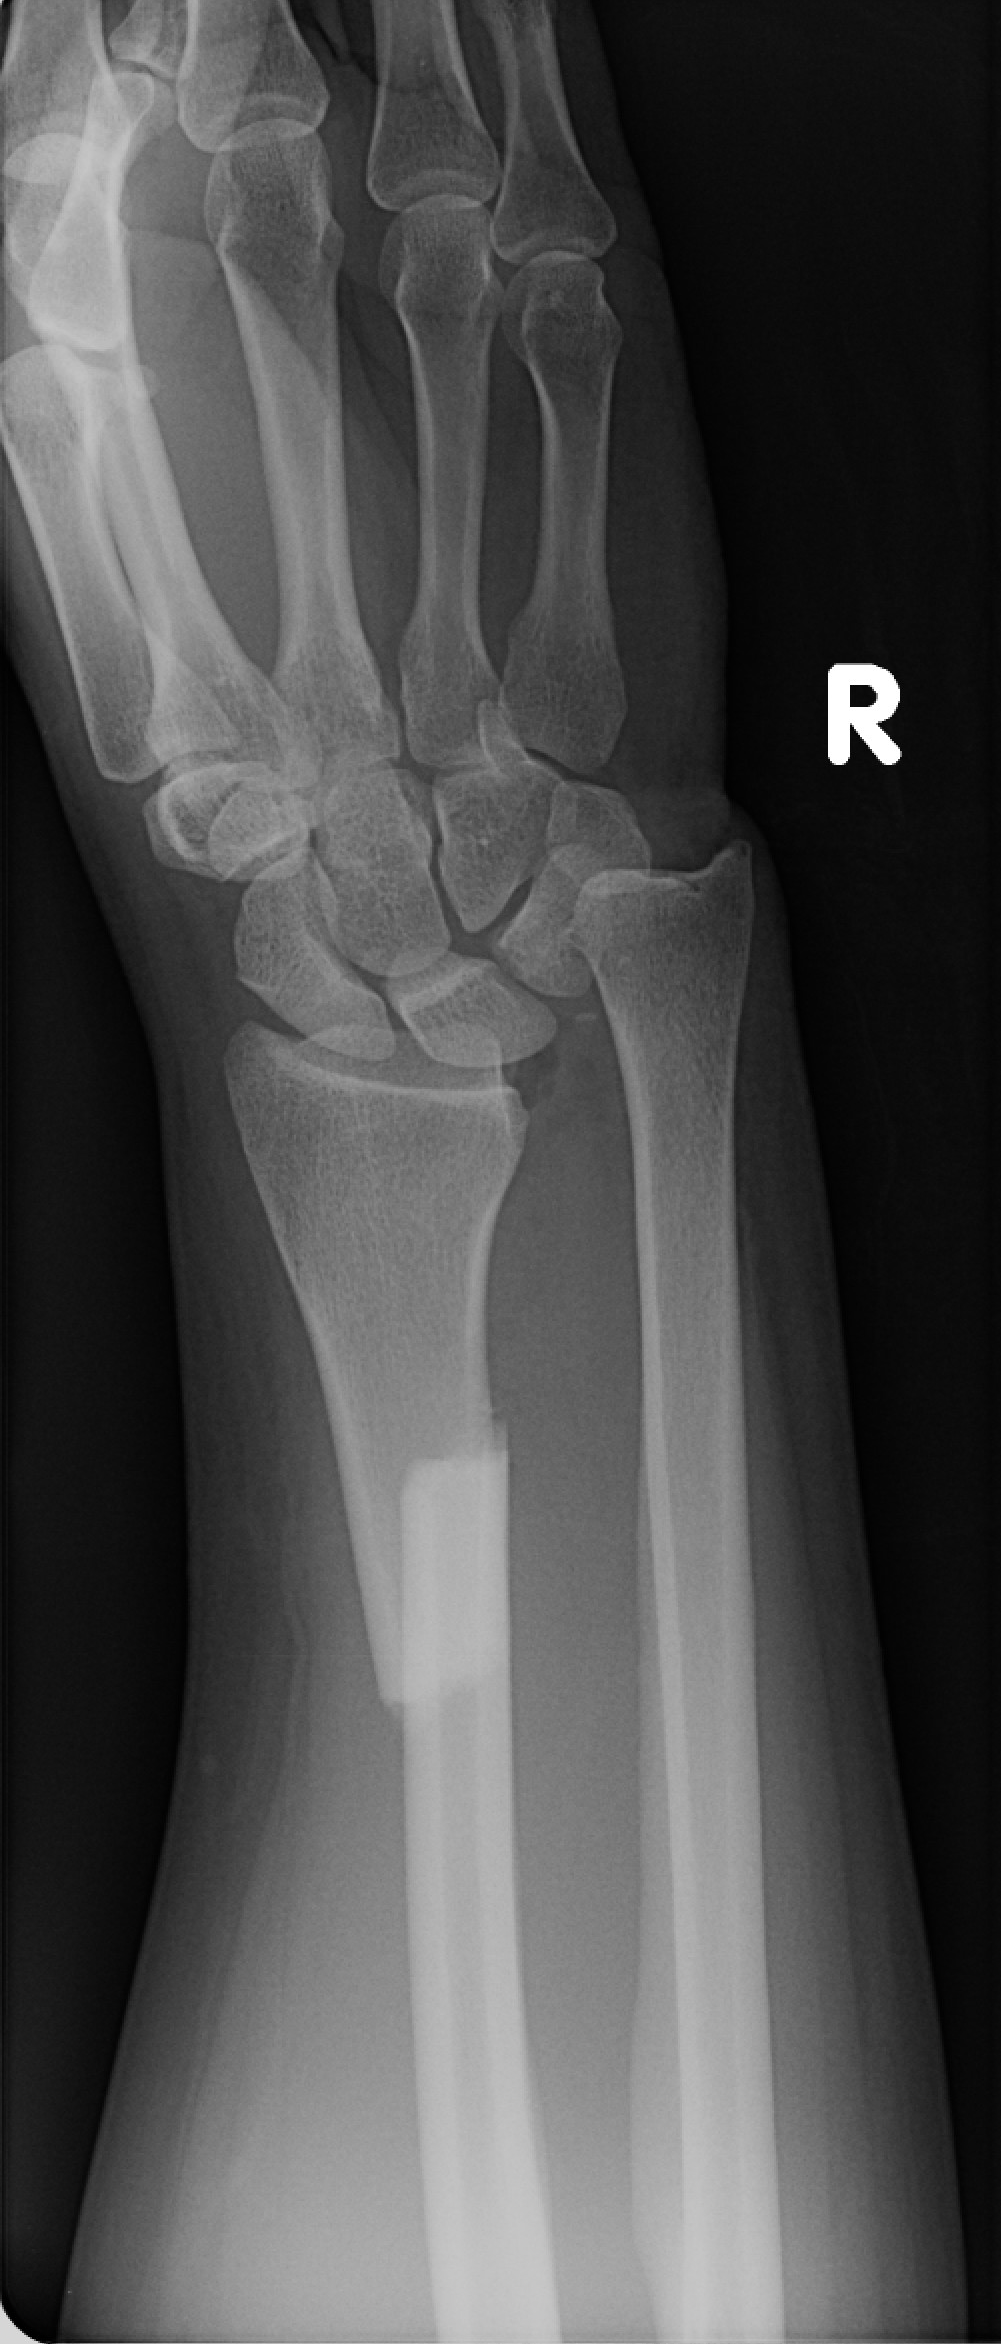

Galeazzi fractures

• Fracture of distal radius with disruption of the distal radial-ulnar joint.

• Type 1 = Dorsal displacement of the radius

• Type 2 = Volar displacement of the radius

• Notable complications: entrapment of extensor carpi ulnaris tendon or extensor digiti minimi tendon

Case courtesy of Alexandra Stanislavsky, Radiopaedia.org, rID: 10961 (Galeazzi case)